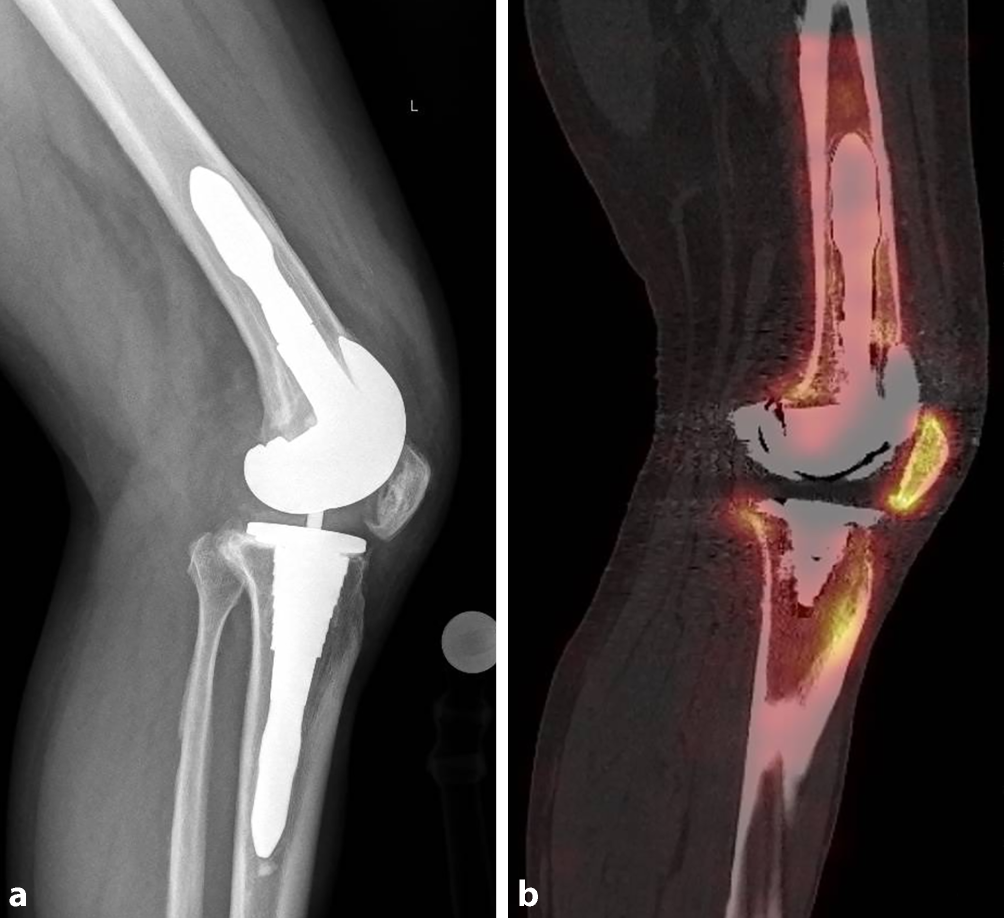

Die kombinierte SPECT- und CT-Bildgebung (Abb. 5; z. B. 99mTc-HDP-SPECT/CT) ermöglicht eine detaillierte Darstellung der Tracer-Aufnahme in Relation zur Gelenkarchitektur, bei guter Reproduzierbarkeit und ist besonders nützlich, wenn konventionelle Bildgebungsverfahren unzureichende Informationen liefern [47, 5052]. Zudem kann die Komponentenpositionierung mit spezifischen Schmerzcharakteristika in Korrelation gebracht werden [36, 51]. In einer Arbeit von Hirschmann et al. konnte eine erhöhte Tracer-Aktivität bei Lockerung, Rotationsfehlstellung oder verändertem Slope mit tibialem, femoralem oder patellärem Tracer-Uptake korreliert werden [35, 47, 53]. Besonders bei Patella baja (Abb. 6) und patellofemoraler Arthrose ist eine erhöhte patellofemorale Tracer-Aufnahme zu beobachten [47, 53, 54]. Entscheidend ist es hier, die Uptake-Muster-Pathologien zuordnen zu können.

Abb. 6

Patella baja, Knie links. Röntgenbild seitlich konventionell (a), SPECT/CT mit Tracer-Uptake (b)